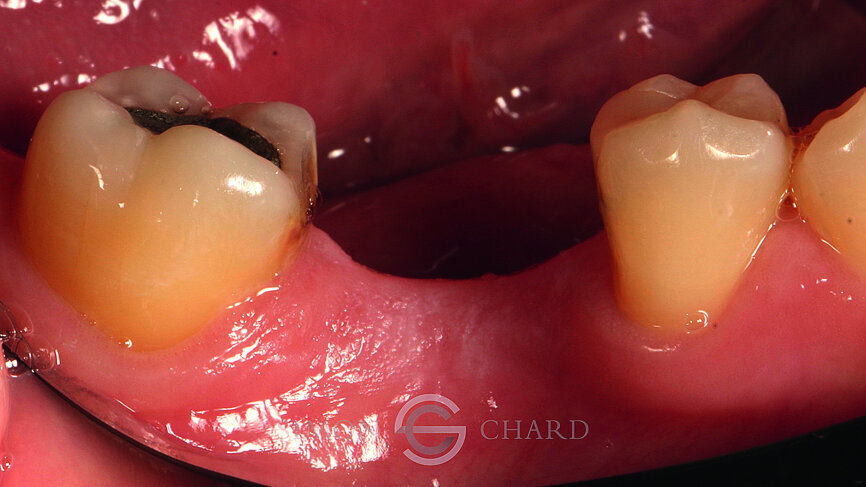

This case report highlights a novel method of restoring implants utilising the modern advances in digital intraoral scanning and chairside milling. It illustrates how an aesthetic single implant retained crown can be provided chairside without the need for analogue impressions (Figs. 1 & 2: Pre-operative condition).

Following a discussion of the options for replacement of LR6, the patient elected for an implant-retained solution. A MegaGen AnyRidge 4 x 10 mm implant was placed utilising a surgical guide for position of the pilot hole. An immediate temporary crown was fabricated using the MegaGen fuse abutment and DMG Luxatemp. A silicone index of the diagnostic wax-up was fabricated and the temporary crown was polished and taken out of occlusion while the implant fully integrated (Fig. 3).

Following 3 months of integration, the patient attended the practice for the restoration of the implant with a definitive crown. During this period, the soft tissue had been given time to mature and a beautiful molar soft tissue profile had formed (Figs. 4 & 5).